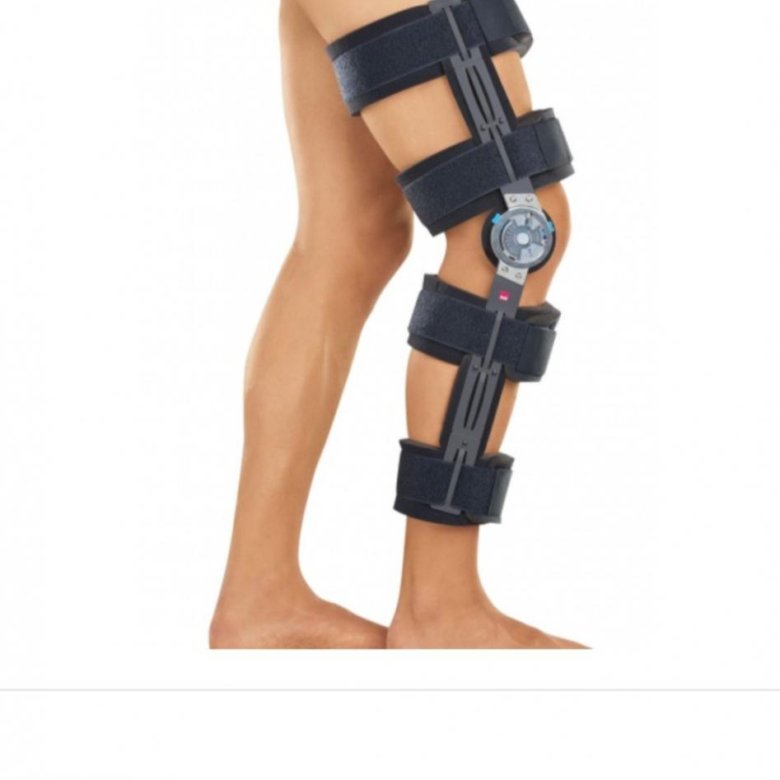

Как выбрать шарнирный брейс на коленный сустав

Раздел: Компас решений